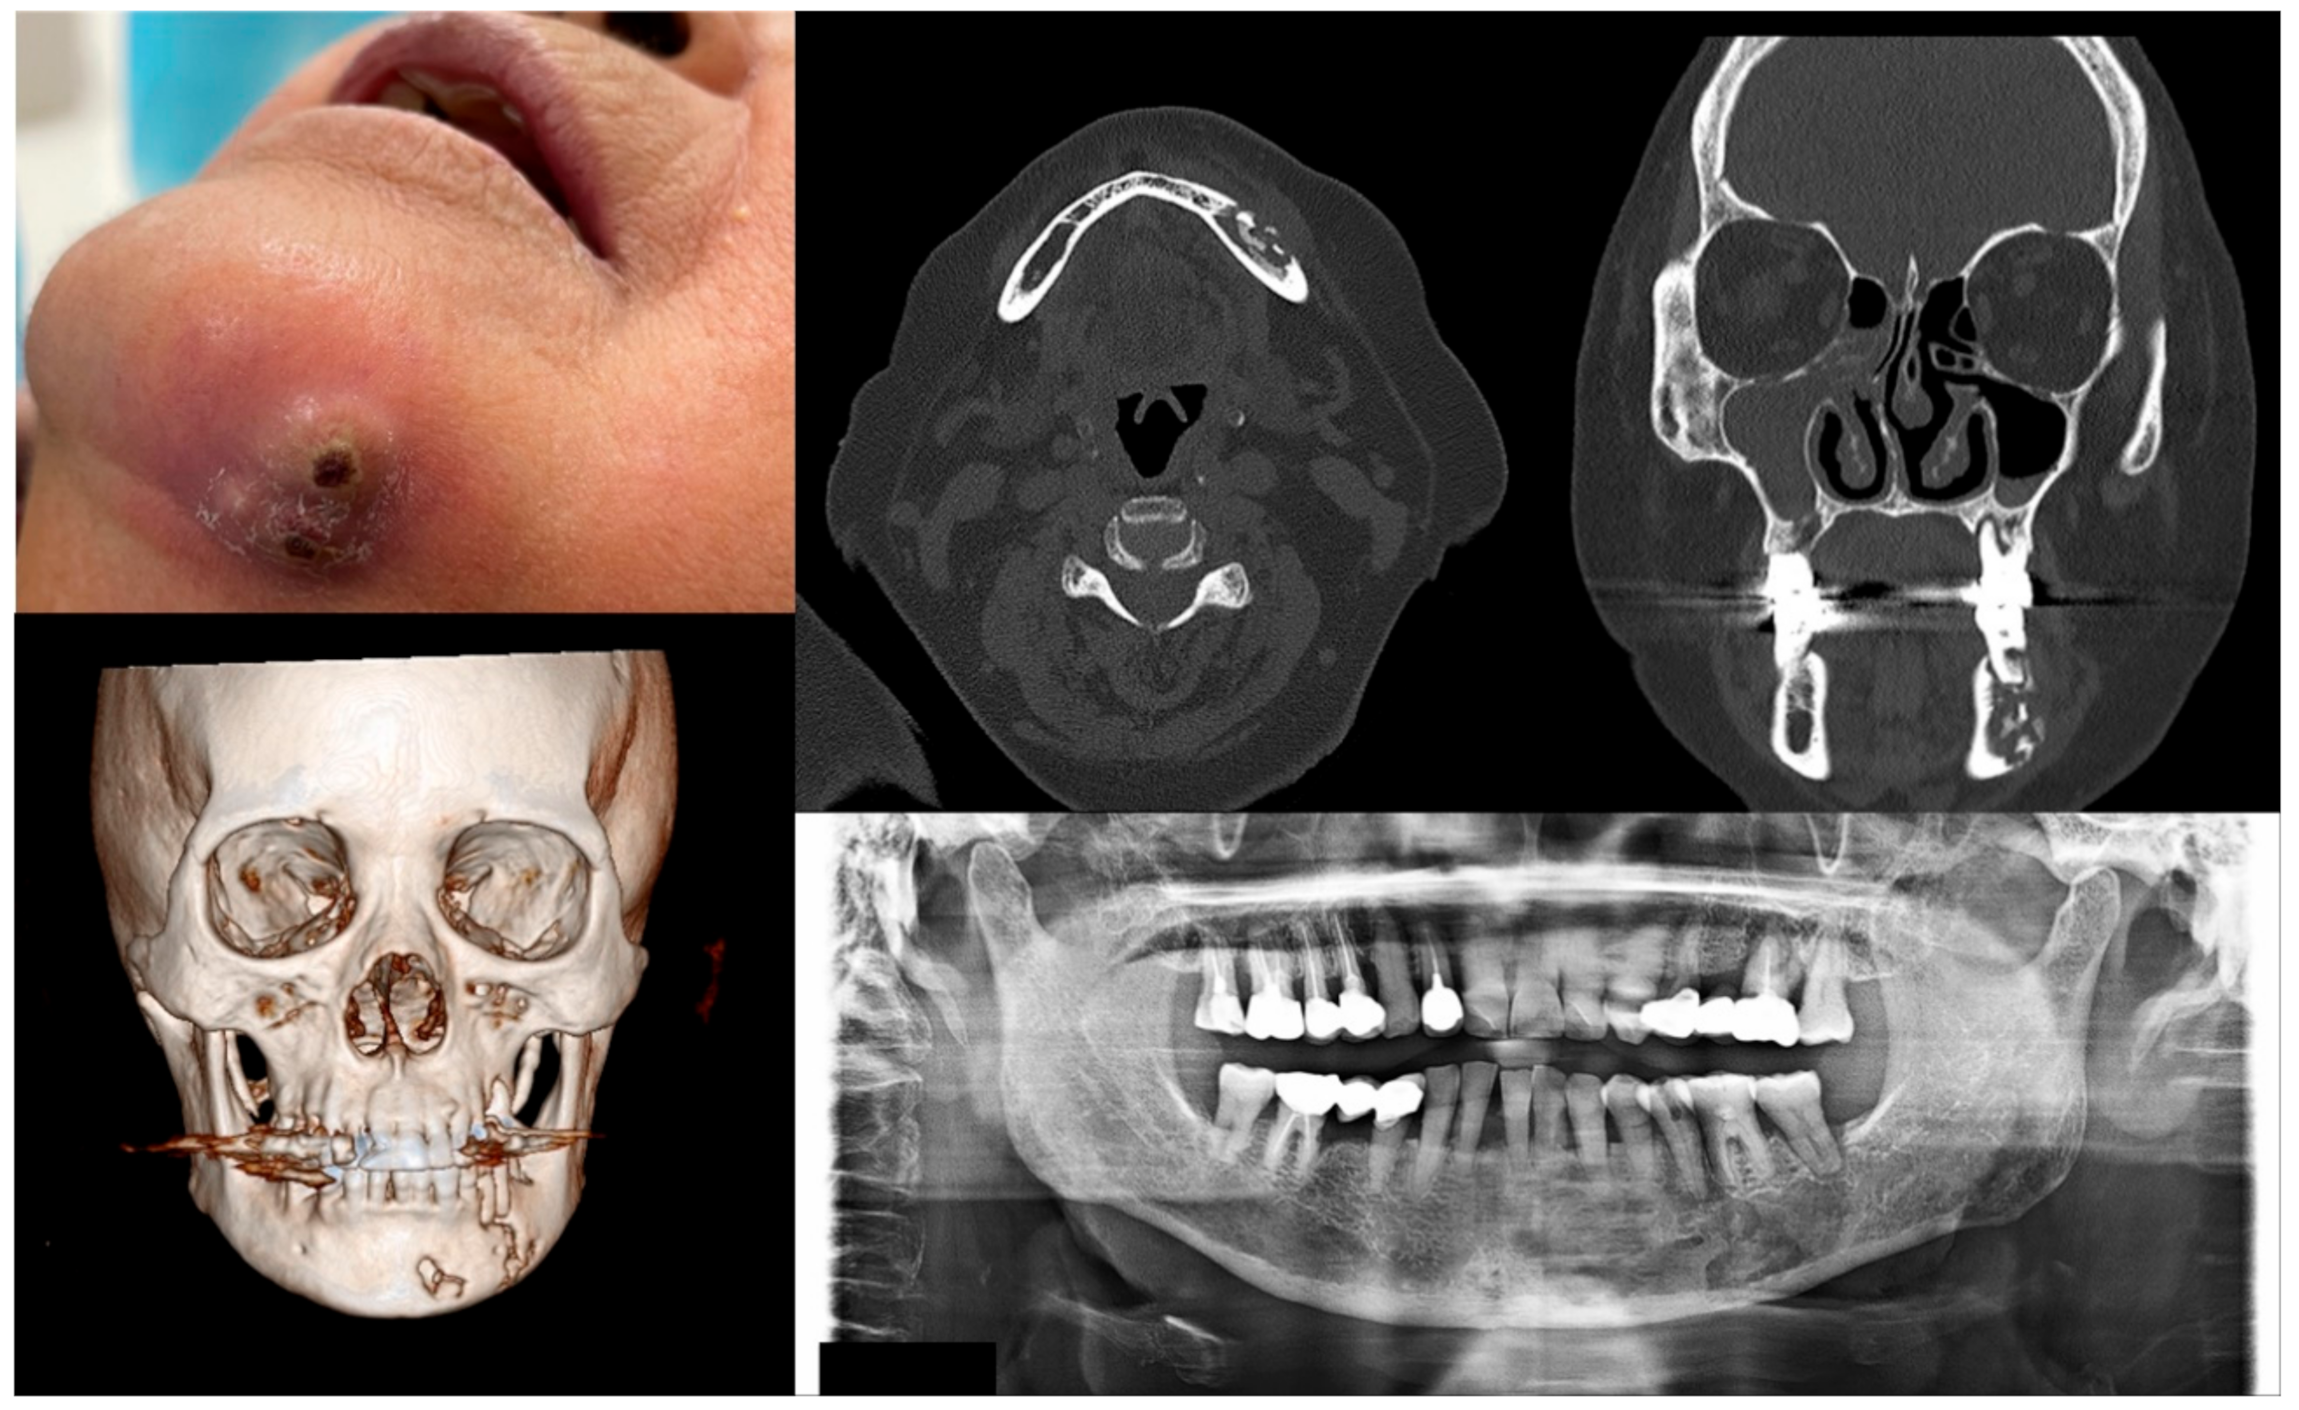

2.1. Staging of MRONJ and Treatment Strategies

| Stage | Clinical Manifestation | Strategies for Management |

|---|---|---|

| At risk | No apparent necrotic bone | Patient education, no treatment required |

| 0 | No clinically necrotic or exposed bone with nonspecific clinical and radiographic findings | Systemic medication, including antibiotics and pain-killers when indicated |

| 1 | Exposed necrotic bone or intraoral fistula with no symptoms and no infection | Patient education, oral antibacterial rinse, close clinical follow-up |

| 2 | Exposed necrotic bone or intraoral fistula showing symptoms and signs associated with infection | Antibacterial oral rinse, systemic medication with antibiotics and pain-killers, debridement reducing the volume of necrotic bone for infection control |

| 3 | Exposed necrotic bone or intraoral fistula showing symptoms and signs associated with infection + exposed necrotic bone invading the inferior border of the mandible or the sinus floor of the maxilla and/or extraoral fistula and/or oroantral fistula | Antibacterial oral rinse, medication with antibiotics and pain-killers, surgical treatment including open debridement/resection for long-term control of symptoms and infection |